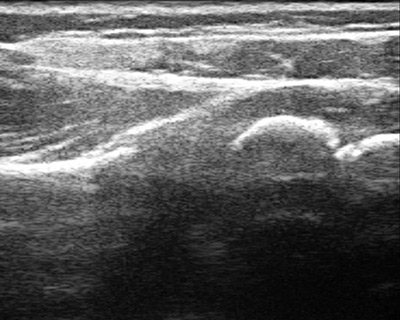

To diagnose shoulder problems in children with BPBI, the current recommendation is to use ultrasound until the child is one-year old. After that, the ultrasound becomes less reliable, and an MRI becomes more appropriate.

Figure 3b: Normal shoulder ultrasound

Many patients come to us too late to implement the teapot splint, and shoulder tightness with internal rotation has already set in. In children less than a year of age, it may be possible to stretch out the shoulder using botulinum toxin to temporarily weaken the muscles that turn the shoulder in, and then to cast the shoulder in a position of external rotation (Figure 4). This has to be done with the child asleep and so requires general anesthesia. Ultrasound is used to confirm that the joint is in place after the shoulder is stretched, and is it also used intermittently after the cast is removed to make sure that the shoulder is growing and developing well. A teapot splint may be used after casting for up to two years during sleep to maintain the shoulder position.